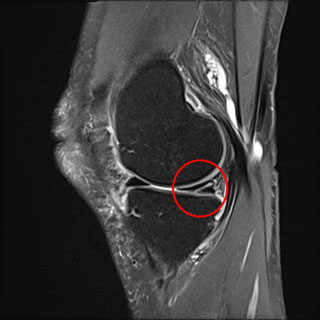

Sehr häufig wird bei dem Verdacht eines Meniskusschadens bei der körperlichen Untersuchung eine Kernspintomographie durchgeführt. Mit Hilfe dieser Untersuchung können Veränderungen am Bandapparat und an den Menisken sichtbar gemacht werden. Auf den traditionellen Röntgenaufnahmen kommen nur die knöchernen Anteile des Kniegelenkes zur Darstellung. Diese lassen nur bedingt Rückschlüsse auf eine Meniskusschädigung zu.